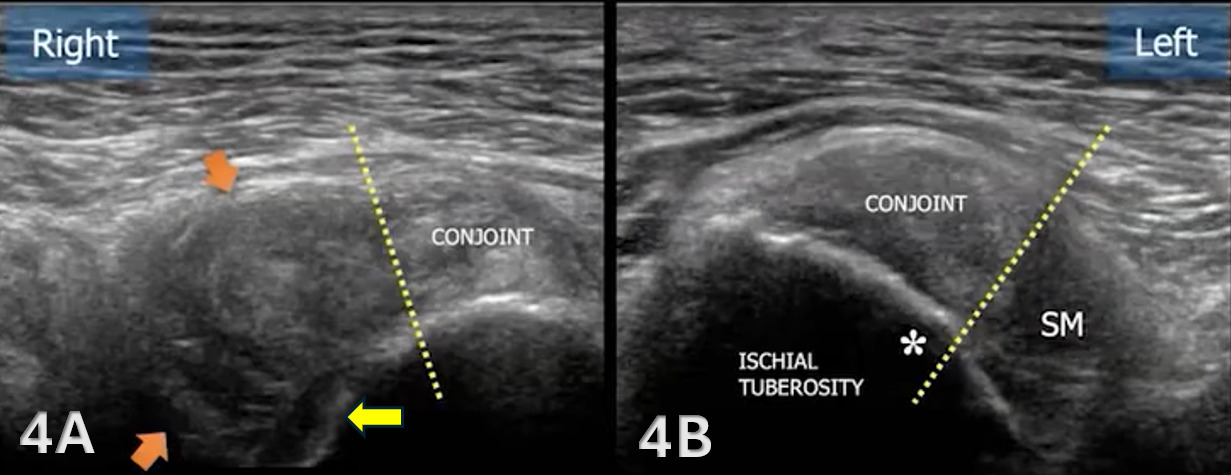

The proximal medial hamstrings consist of both the semitendinosus and semimembranosus, and the proximal lateral muscle, the biceps femoris, all of which originate on the ischial tuberosity.8 The biceps femoris long head and the semitendinosus muscle originate from a conjoint tendon at the medial posterior aspect of the ischial tuberosity, while the semimembranosus attaches more laterally and anteriorly.9,10

The starting point for examining the proximal hamstring tendon and muscle is at the osseous landmark – the ischial tuberosity.12,13,17–19 The ischial tuberosity can almost always be palpated, giving the examiner a perfect location to begin their scan. The proximal hamstring can be scanned in both the long axis (LAX) and the short axis (SAX). In the LAX view, depending on the probe width and size, one should start proximally to visualize the hyperechoic reflection of the bony cortex of the ischial tuberosity, with its large acoustic shadow underneath. In LAX, the proximal hamstring tendon fibers of the long head of the biceps femoris and the semitendinosus conjoint tendon should be easily seen coming off the attachment of the ischial tuberosity with a clear hyperechoic fibrillar structure running distally from the insertion site on the anterior lateral origin of the ischial tuberosity. The semitendinosus fibers can be easily seen as they reach the ischial tuberosity directly. Lateral to the hamstring muscle complex, the sonographer will see the sciatic nerve that appears as a fascicular, flattened structure that descends between and deep to the long head of the biceps femoris and semimembranosus tendon.1 The probe can be turned 90 degrees for viewing in the SAX. If the probe is moved slightly distally in the SAX view, the biceps femoris will appear as a triangular shape. As the examiner moves distally along the biceps muscle belly, the size will decrease until it appears to disappear. In both views, some toggling may be required to reduce anisotropy.